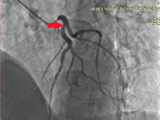

患者男性,52岁,1周前(2018-4-10)突发胸痛3小时,伴大汗,心电图前壁导联明显的ST段弓背向上抬高,以及心肌坏死标记物存在有意义的升高,明确诊断为:冠心病,急性前壁心肌梗死,遂来我院就诊,我科启动绿色通道,为患者实施急诊冠脉造影检查